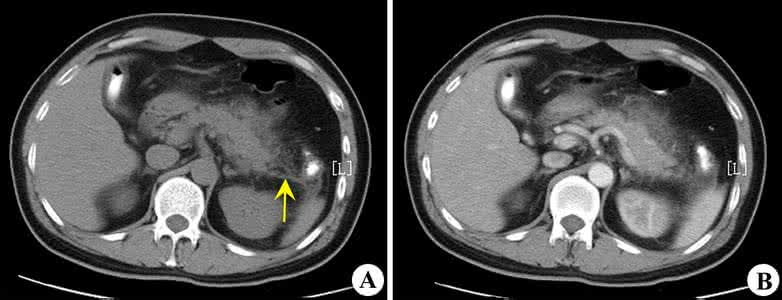

急性胰腺炎影像